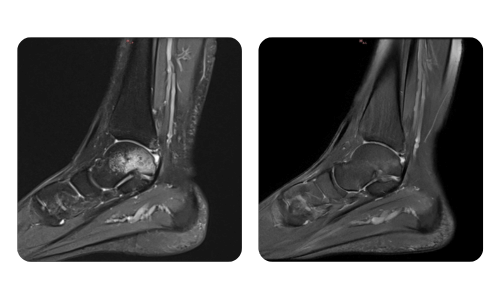

The progress of our patients, measured before and after hyperbaric therapy, reflects the efficiency and positive impact of the treatment. Discover documented results of hyperbaric therapy at Hyperbarium Oradea clinic, based on clinical evaluations and objective data that highlight significant improvements in various conditions.